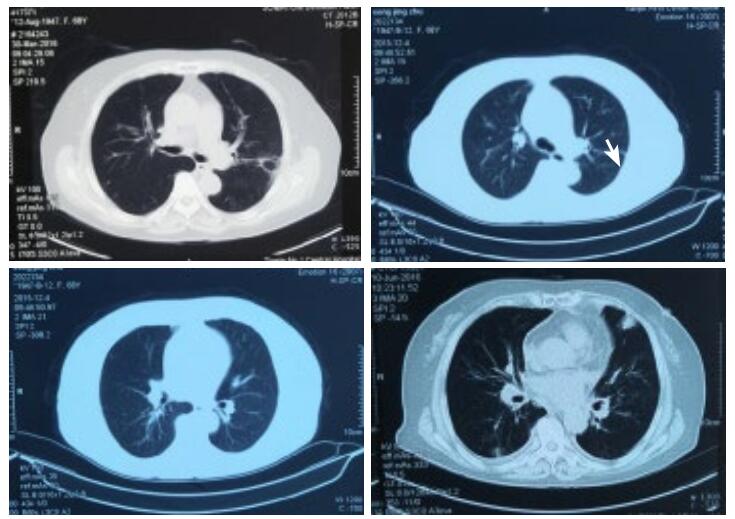

第1天,心脏超声提示:左房38 mm,左室舒张末内径50 mm,射血分数50%。左室下壁后壁运动减低,左室收缩功能减低,心律失常,二、三尖瓣轻度反流。血化验回报:血常规:白细胞(WBC)15.32×109/L,中性粒细胞(NEUT)比例55.64%,嗜酸性粒细胞(Eosinophil,EO)比例18.81%(绝对值2.88×109/L)。入院后给予左西孟旦等药物对症治疗。第3天,血常规回报:WBC 13.07×109/L,NEUT比例44.0%,EO比例42.0%(绝对值5.49×109/L)。第4天,复查血常规回报:WBC 12.6×109/L,NEUT比例43.6%,EO比例36.9%(绝对值4.6×109/L),复查cTnT 4.16 ng/mL;NT-proBNP 13 840 pg/mL。患者症状略缓解。追问病史:入院前1年曾3次就诊于外院,且反复多次出现EO异常升高,最高2.32×109/L,动态对比胸部CT情况可见游走性斑片影,且入院前1周行冠脉CTA检查未见异常。故考虑Löffler心内膜炎可能。第5天,给予甲强龙40 mg静脉,第6天复查血常规WBC 7.2×109/L,NEUT比例87.2%,EO比例0.5%(绝对值0.0×109/L)。持续给予甲强龙40 mg静脉5 d,第10天复查血常规WBC 9.5×109/L,NEUT比例70.1%,EO比例0.7%(绝对值0.1×109/L);cTnT 2.24 ng/mL;NT-proBNP 6 481 pg/mL,住院期间查ANCA阴性,曲真菌抗体阴性、C反应蛋白、降钙素原、体液免疫、风湿全项均正常。入院后11 d症状好转出院。

| 图 2 入院前1年多次胸部CT情况(箭头所示游走性斑片影) |

患者因心前区不适入院。急诊查cTnT及NT-proBNP明显异常,提示心肌损伤、心功能不全诊断明确。但入院后反复复查血常规,EO均明显升高,且患者入院前1周行冠脉CTA未见异常,加之入院后心肌酶、心电图不符合AMI动态演变过程。另外患者1年内多次入院均出现EO均异常升高(均大于 > 1.5×109/L),提示存在嗜酸性粒细胞增多症,胸部CT可见游走性斑片影,提示存在嗜酸性粒细胞增多综合征[1]。尽管未做心肌活检,但患者具有心血管系统、呼吸系统损害,EO计数反复大于 > 1.5×109/L,故笔者认为Löffler心内膜炎诊断明确。